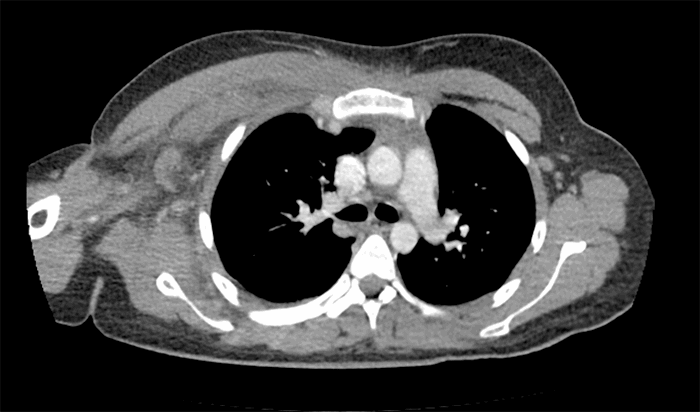

Figure 1. Axial CT Imaging Demonstrating Subpectoral and Axillary Soft Tissue Edema with Lymphadenopathy. Published with Permission

Our patient initially presented with five days of severe right-sided chest and shoulder pain. Examination showed tachycardia, swelling, and pain out of proportion to the exam without any skin changes or crepitus. CT scan revealed diffuse soft tissue swelling involving the pectoralis muscles and axillary lymphadenopathy without subcutaneous emphysema. Within hours of admission, she became unresponsive and refractory to massive crystalloid infusion and vasopressor support, so she was taken emergently to the operating room. Surgical exploration demonstrated extensive soft tissue and muscular necrosis. Tissue cultures demonstrated S. pyogenes, and antibiotic coverage was narrowed with intravenous immunoglobulin as an adjunct therapy. She underwent multiple debridements, and we were able to obtain primary wound closure via sequential partial closures.